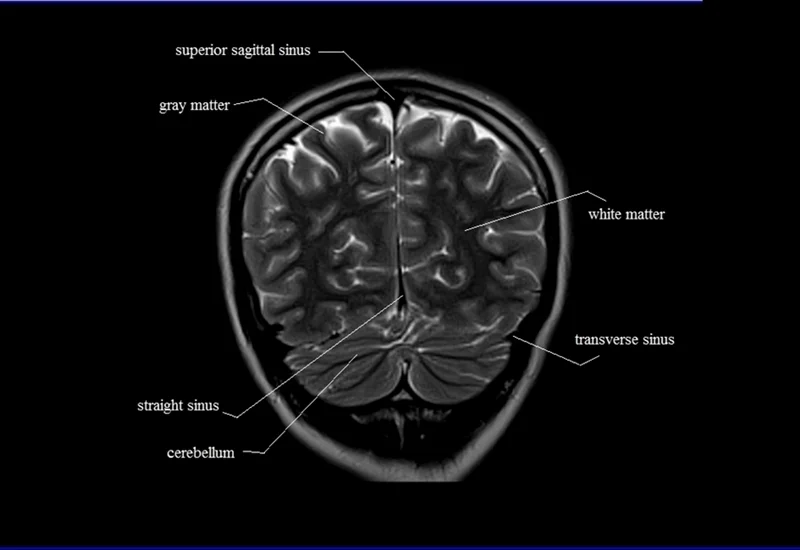

MRI brain anatomy helps doctors visualize the brain’s intricate structures with remarkable clarity. The main components of the brain that can be observed through MRI imaging include:

5. White and Gray Matter

- White matter consists of nerve fibers that transmit signals between different parts of the brain, while gray matter contains the neurons responsible for processing information.

- MRI can show the health of these tissues and identify changes that may signal conditions such as multiple sclerosis or stroke.